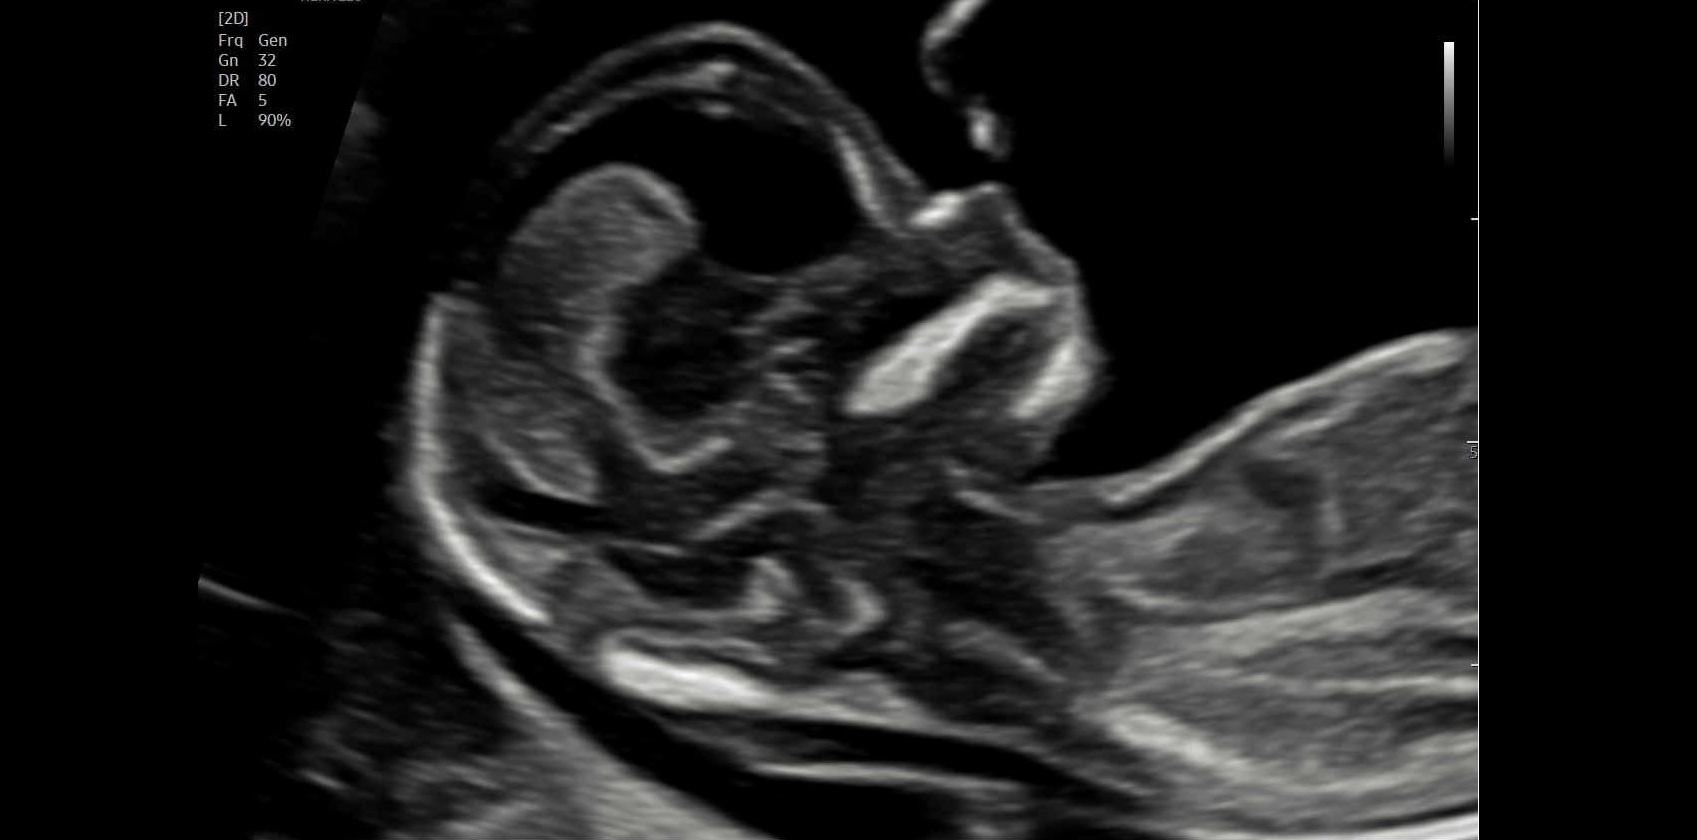

Ersttrimester-Screening: 12-13 SSW

In diesem detaillierten Ultraschall können wir neben der Nackentransparenz bereits die vollständig angelegten Organe Ihres Kindes untersuchen. So erhalten Sie schon früh einen bildlichen Eindruck der ersten Entwicklungsschritte.